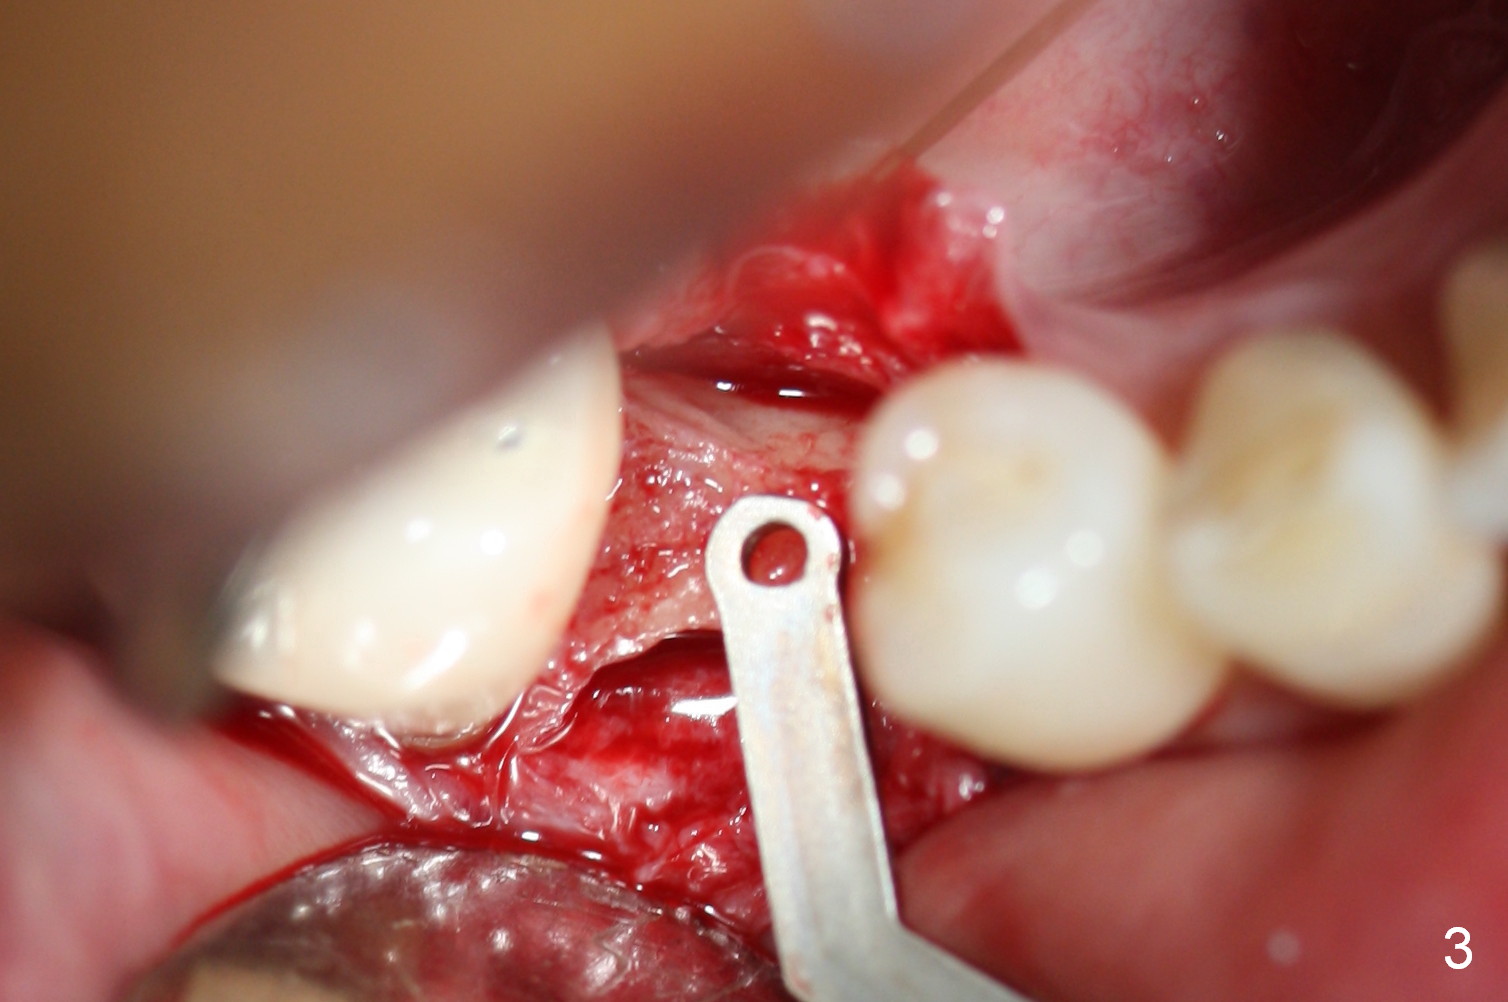

Preop photo shows the distal inclination of the tooth #28 (Fig.1). The distal surface of the latter is reduced before incision for implant placement at #29 (Fig.2). The buccolingual width is approximately 4 mm, as compared to 3 mm implant positioner (Fig.3). After 1.2x10 mm osteotomy (Fig.5), the mesiodistal cortical bone is removed with a small high-speed fissural bur (Fig.4). When a 2.5x12(2) mm 1-piece implant is placed (Fig.6), there is no buccal (Fig.7) or lingual plate perforation. There is no postop paresthesia. There is mild bone loss distal 4 months postop (Fig.8 *). Take photos before and after permanent crown cementation to show increase in ridge width after bone graft and improvement in gingival health after provisional modification. Take PA and/or BW post cementation to show that the distal bone resorption (Fig.8 *) is partially due to angulation. No continuous bone loss 15 months post cementation (Fig.9). There is mild bone resorption mesially 2 years 3 months post cementation (Fig.10). The soft and hard tissues remain healthy 4 years 3 months post cementation (Fig.11,12).